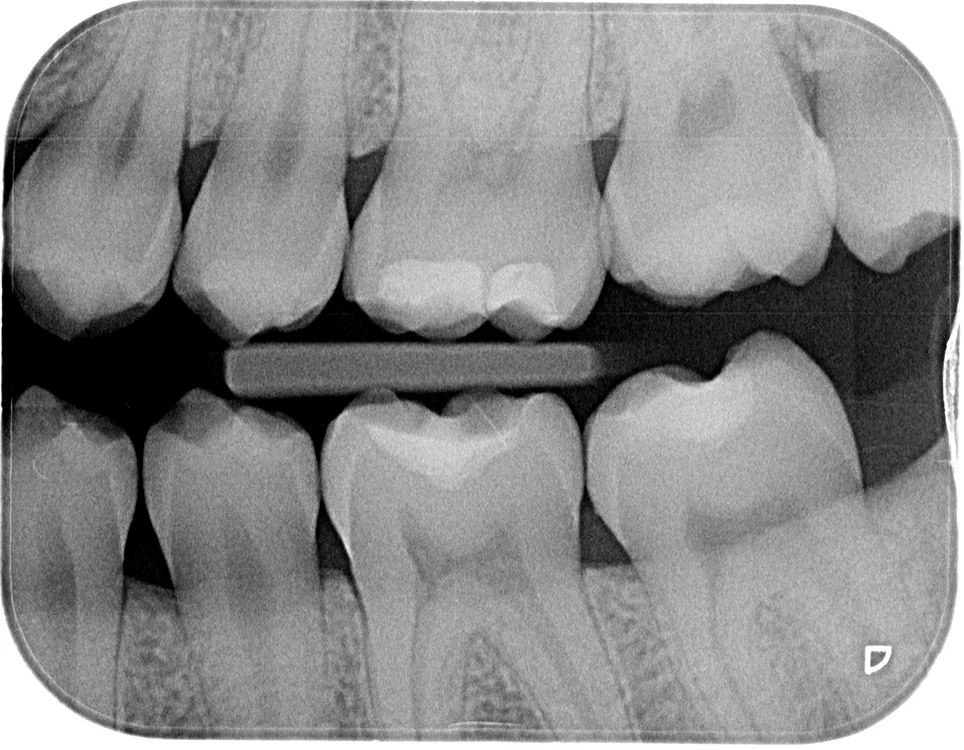

Röntgenologischer Befund

Das OPT (Abb. 1a) gibt keinen Anhalt auf nicht zahnverursachte Prozesse, alle vier Weisheitszähne sind vorhanden und retiniert. Die Bissflügelaufnahmen (Abb. 1b und c) zeigen insuffiziente konservierende Versorgungen an den Zähnen 26, 36, 37 und 46 sowie okklusale Karies an Zahn 16.